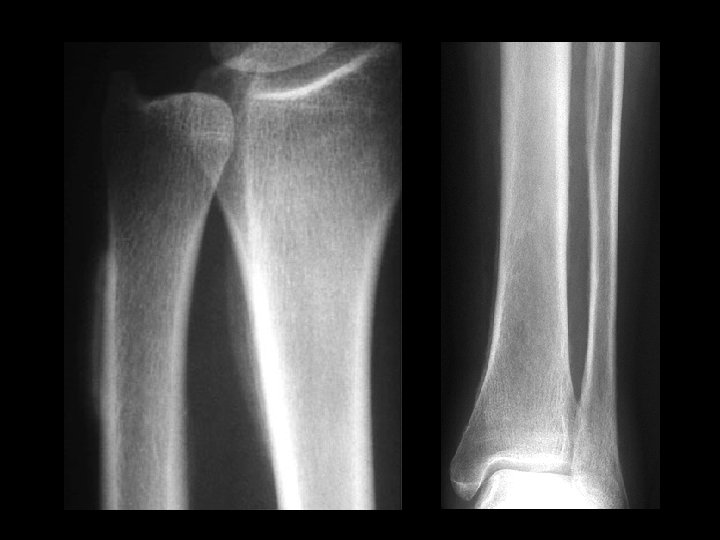

Melorheostosis • • • Findings: – Peripheral hyperostosis of the tibia producing a wavy sclerotic diaphyseal contour Rare bone disorder of childhood “candle wax” dripping down the bone appearance presents with PAIN and joint swelling ddx: – Paget’s – myelofibrosis – renal osteodystrophy – sclerotic mets